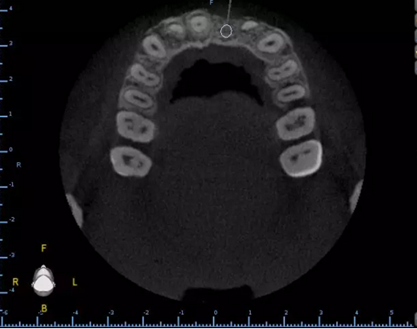

1.術(shù)前CT

2.術(shù)前植體設(shè)計(jì)